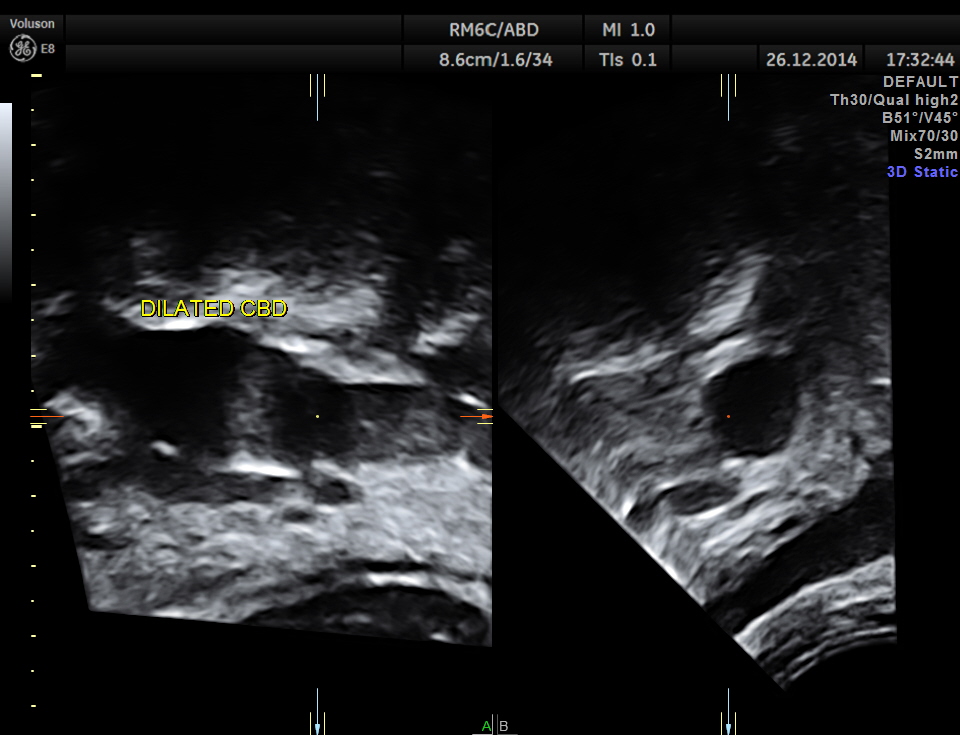

grossly dilated common bile duct.

3 d reconstruction of extra hepatic CBD